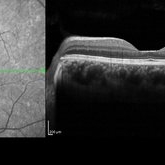

Peripheral Retinoschisis

Jul 26 2018 by Olivia Rainey

Optical coherence tomography of a 49-year-old male with non-progressive peripheral retinoschisis of his left eye. Patient was asymptomatic and had no prior trauma or surgery to his eye. Recommended observation at this time.

Photographer: Olivia Rainey

Imaging device: Heidelberg Spectralis

Condition/keywords: Heidelburg Spectralis, left eye, optical coherence tomography (OCT), retinoschisis